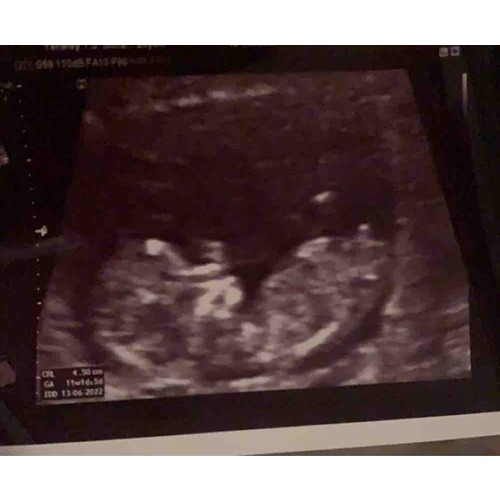

Hopelijk ziet iemand iets x

Iemand ?馃槏

Meisje 馃懅